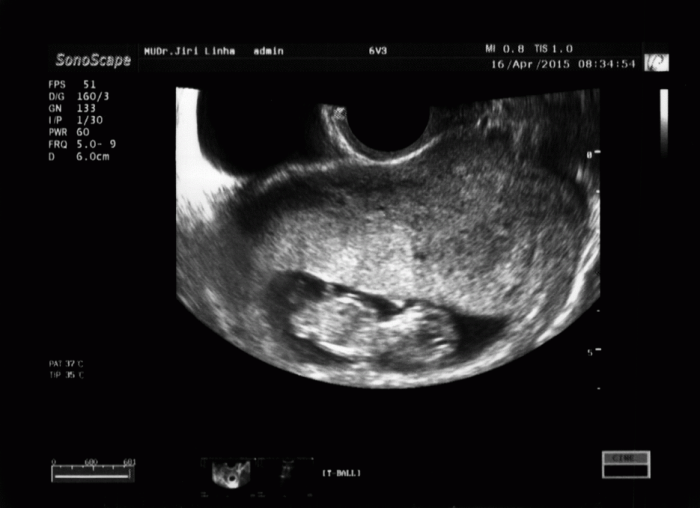

Kacabo, to je zážitek, viď :) My máme doma 15 ČT a když příjde na svět nový přírustek, je to vždycky nádherné. Jinak jsem si dnes řekla o fotku z UTZ a musím říct, že mimísek je pěkný cvalík :D Byla jsem kvůli špinění 14 dní na nemocenské, ale musela jsem ji ukončit, protože mi vážně nic nebylo a v práci už byli nervózní :D Nikdy kdem nechyběla víc jak týden. A co vy? Zvládáte?